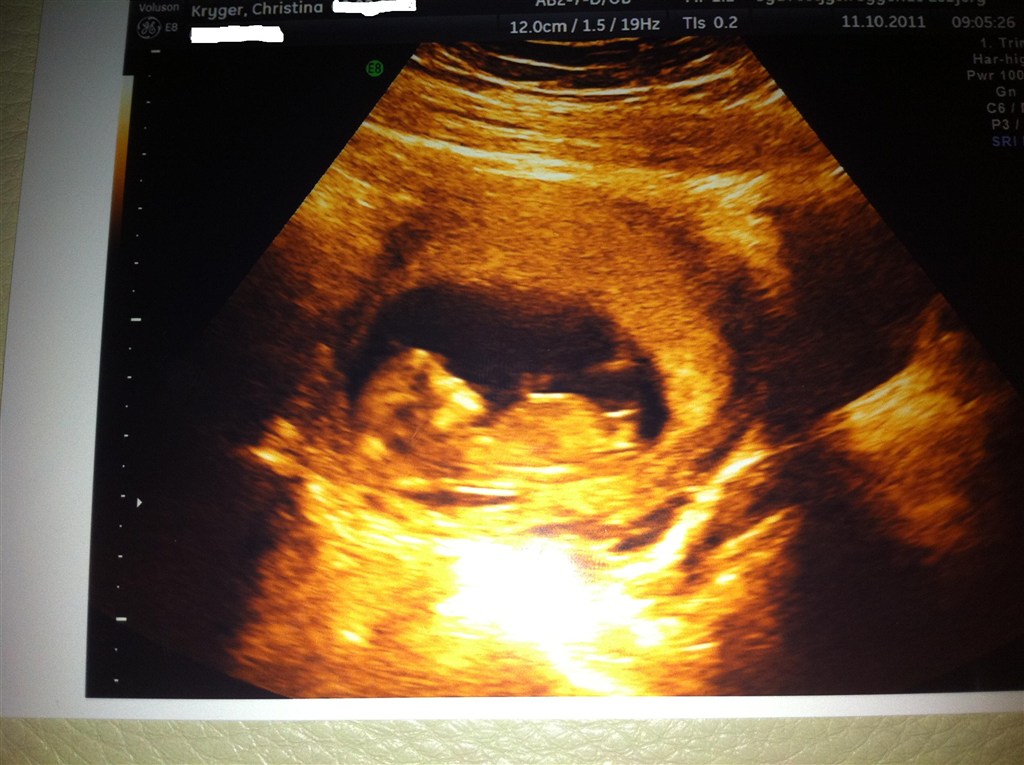

så har vi jo næsten termin samtidig hvor spændende

Ja vi er da tæt på hinanden, blev idag sat 4 dage tilbage - så havde først termin den 22 april, men nu rykket til den 26...